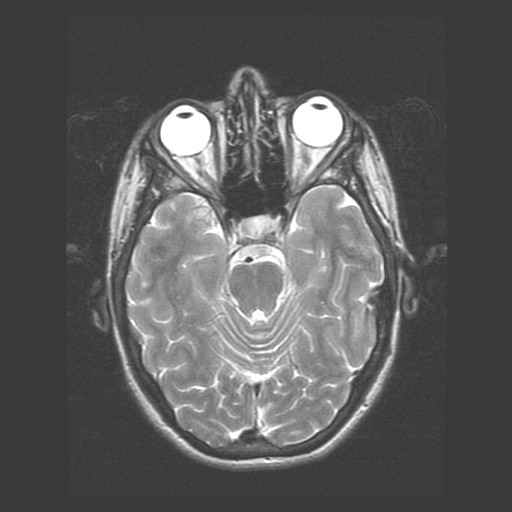

Schedel